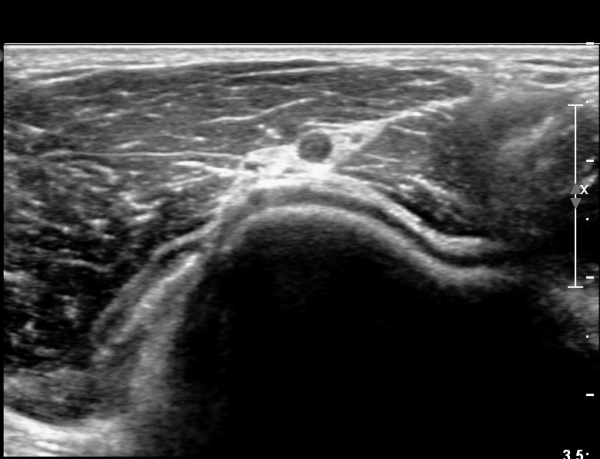

ŽÃËÀÚ¸¦ ¸»´ÜÀ¸·Î Á¶±Ý À̵¿ÇÏ´Ï Èİñ°£ ½Å°æÀÌ ÀÛ¾ÆÁö°í(»çÁø 2),